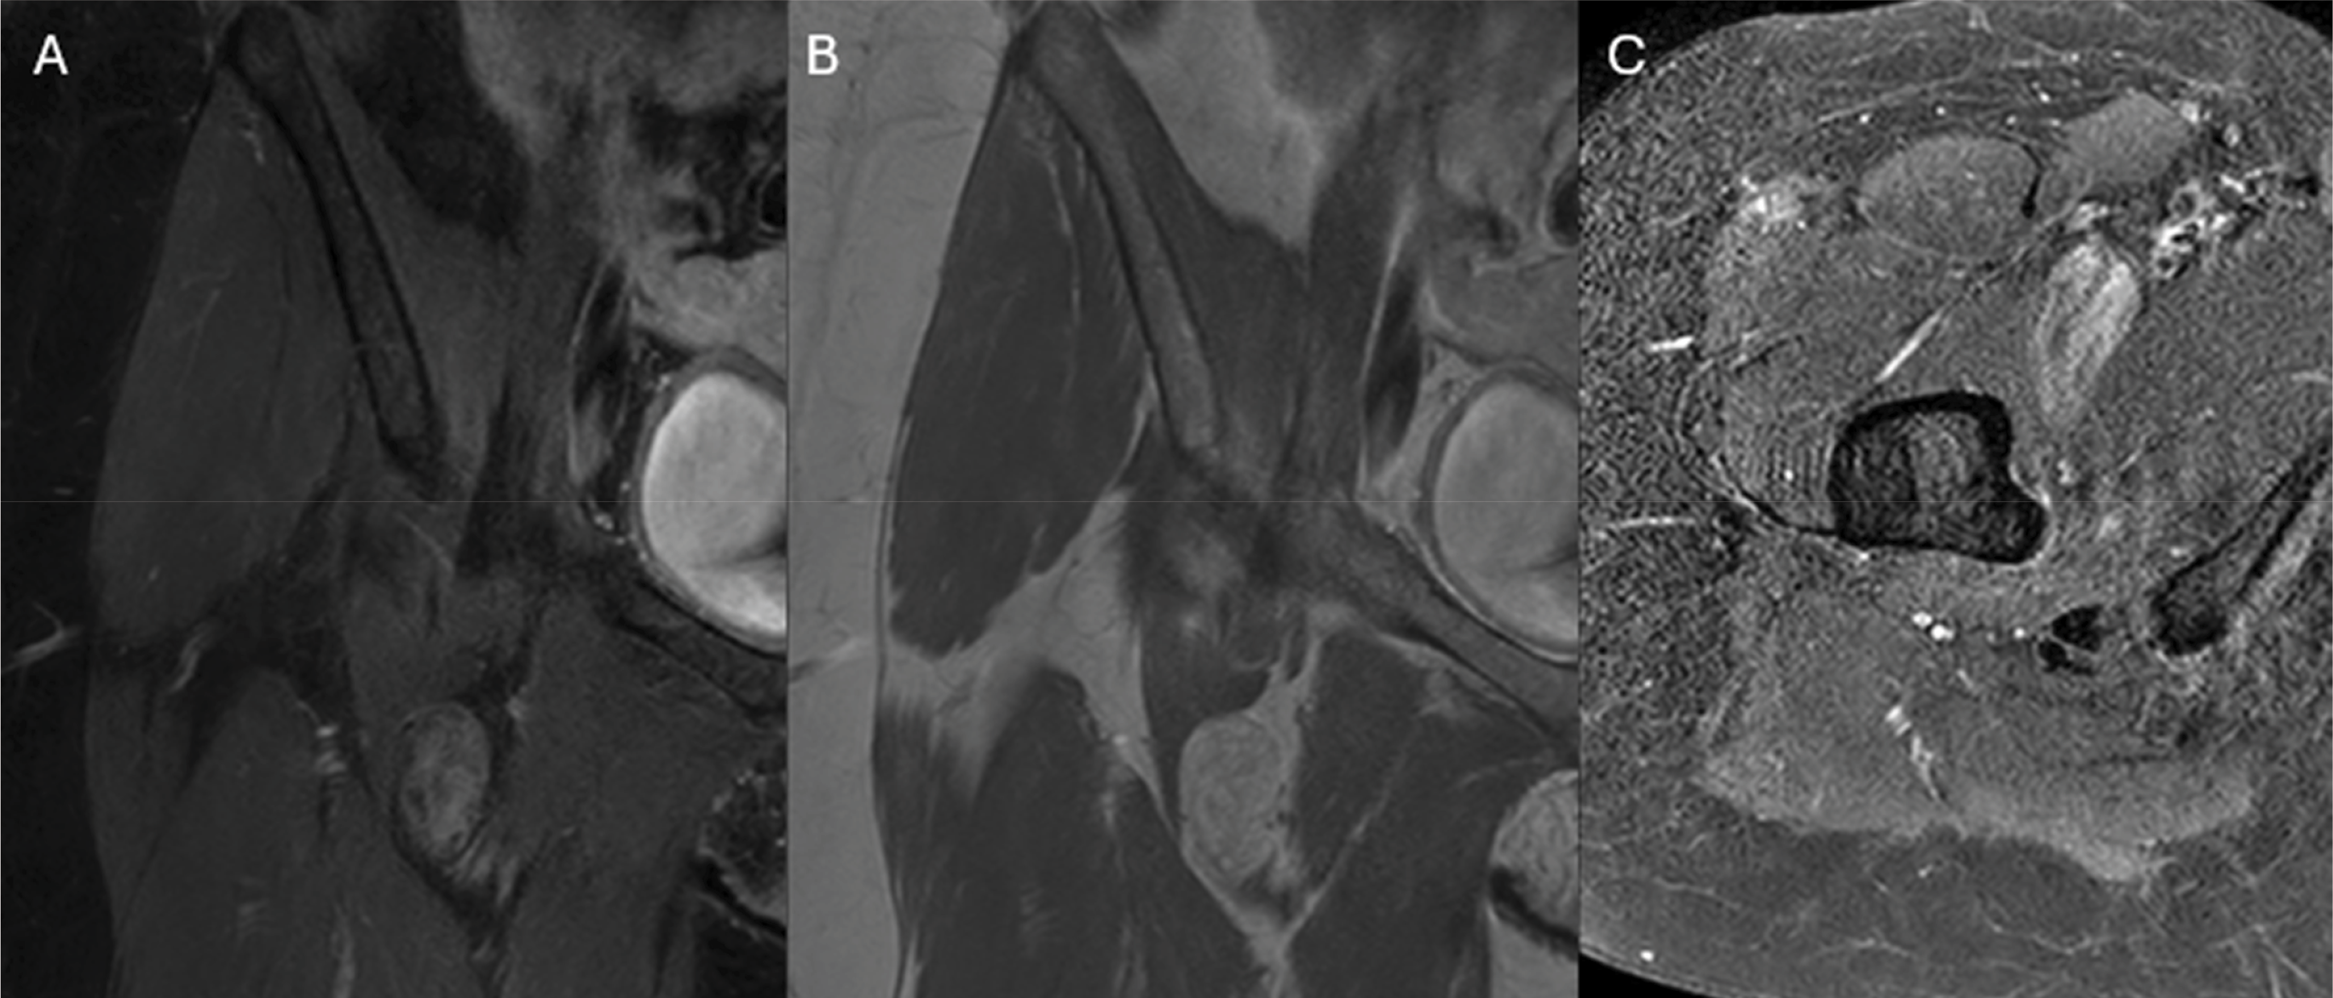

Figure 3

Coronal post‑contrast enhanced images (A and B) and axial post‑contrast SPIR images demonstrate enhancement of the regions of low fat‑content.